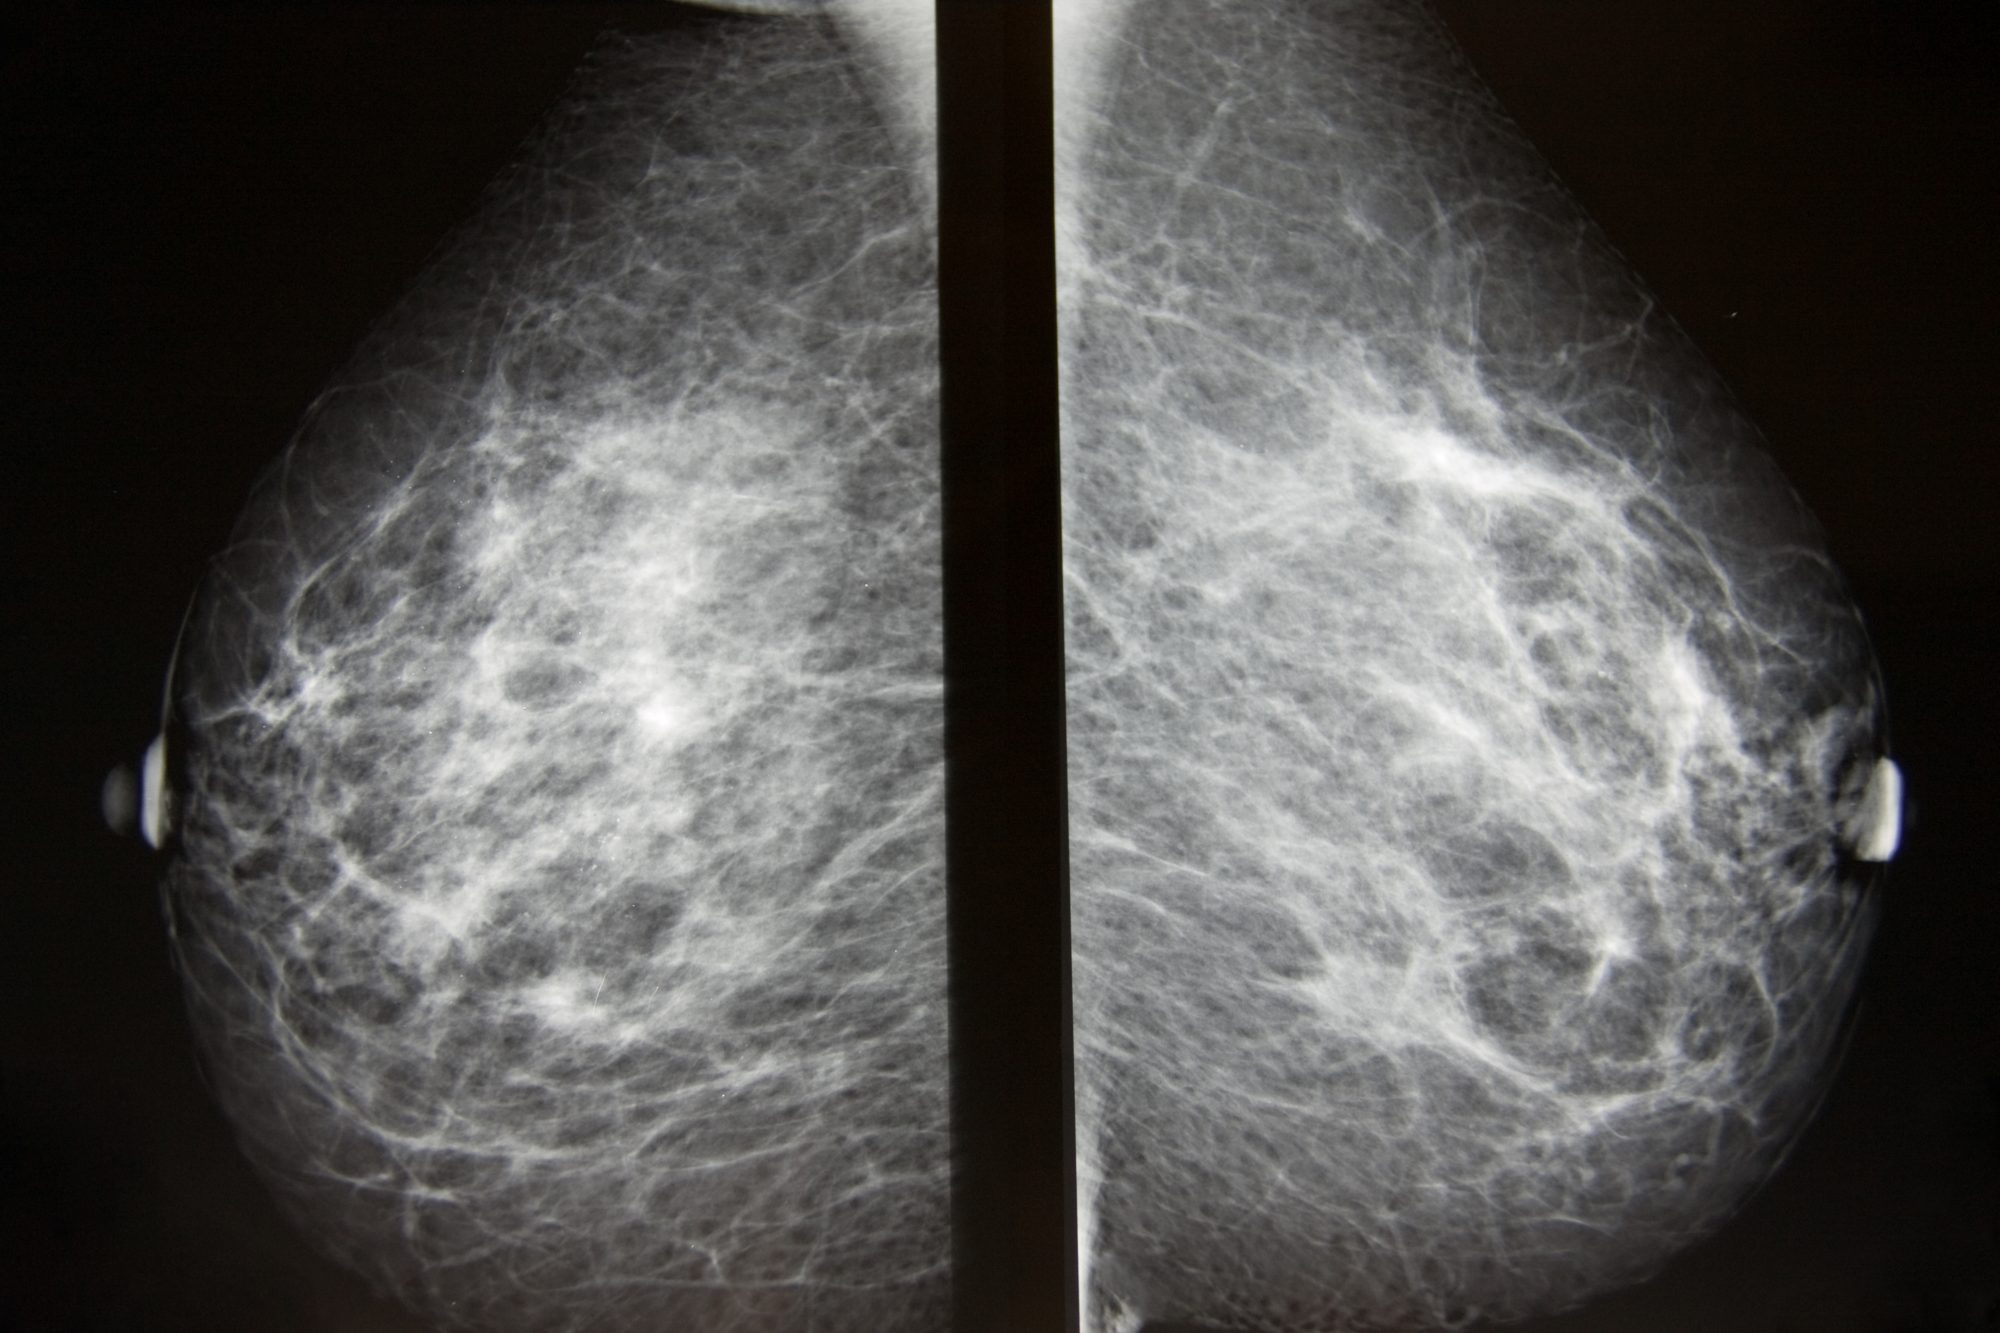

Феномен гипердиагностики в маммографии: примеры и иллюстрации

Раздел: Образы вокруг